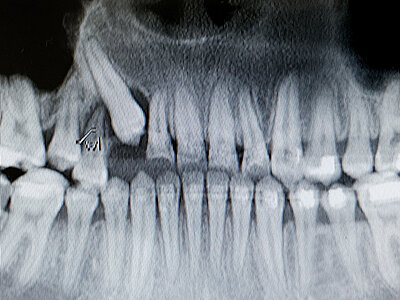

zahnentfernung

Ein minimal-invasiver oder chirurgischer Eingriff, bei dem wir routiniert beschädigte oder erkrankte Zähne entfernen.